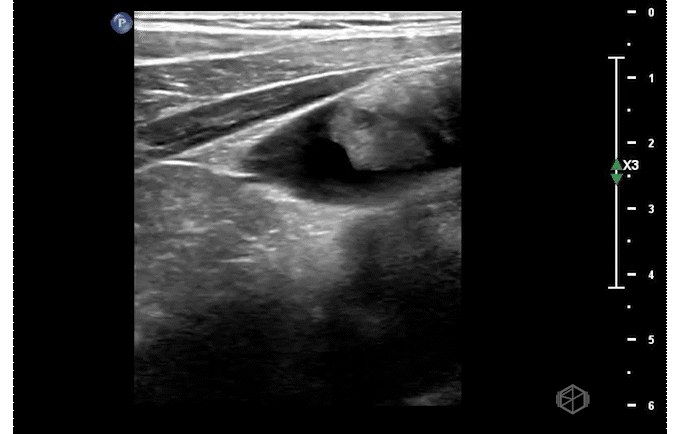

Our first SonoProp goes to Dr. May Ali. Dr. Ali was doing a scan on an 11-year-old male with RLQ pain. The patient had minimal diffuse abdominal tenderness and right lower quadrant tenderness. The following are clips from the scan:

The scans show small-to-moderate free fluid in the abdomen. The appendix is not visualized. The patient had a radiology ultrasound that demonstrated a partially visualized normal appearing appendix with no ancillary findings to suggest appendicitis. Small volume free fluid in the right lower quadrant with small volume perihepatic free fluid. Labs were normal with a normal ESR and CRP. The patient was evaluated by surgery and discharged home with close follow up with his primary care doctor.

Diagnosis — Pediatric abdominal pain with free fluid, likely gastroenteritis